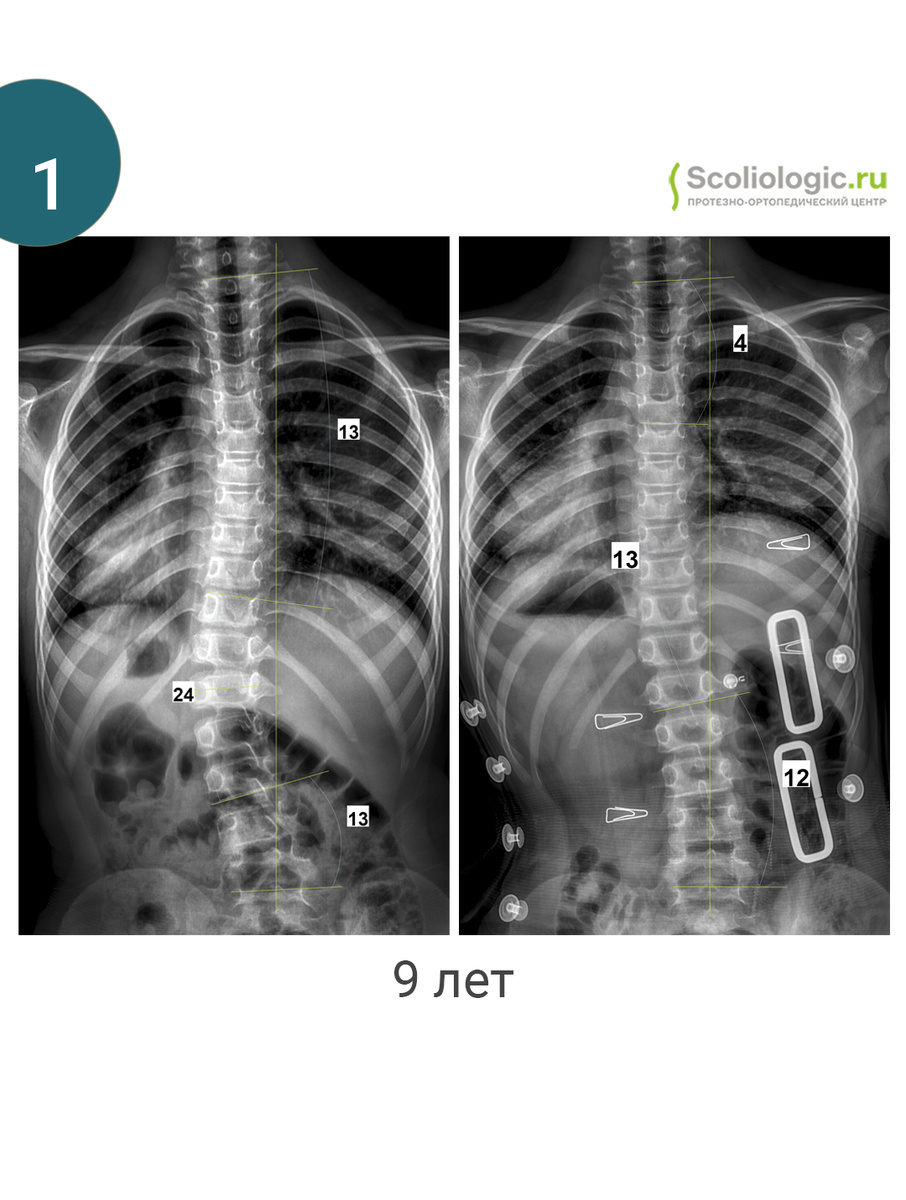

На фото представлены пациенты одного дня и их первые результаты в корсете.

Да, в большинстве случаев коррекция составляет от 25 до 50 % (хотя, это только математика). Но есть и другие случаи.

Фото 1. Очень важно не уйти в гиперкоррекцию и маленькими шажками исправлять баланс.